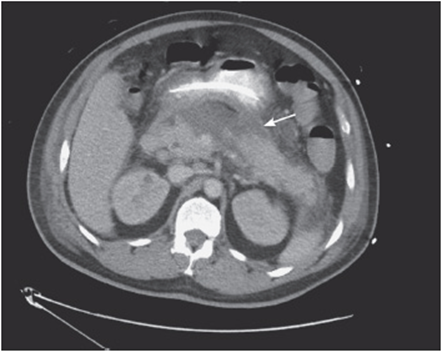

v. Check the liver and biliary tree:

• Look for any irregularities in the liver parenchyma, or any air in the biliary tree.

• Look for subcapsular hematomas or liver lacerations in trauma (see Figure 56-5), and for liver nodules in a patient with a history of malignancy.

Figure 56-5. Splenic laceration caused by a motor vehicle crash.